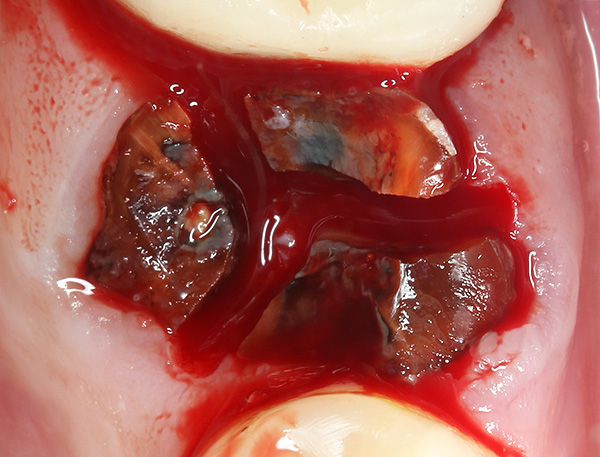

A fotografia abaixo mostra um exemplo de um dente serrado antes da remoção em três partes usando uma broca: